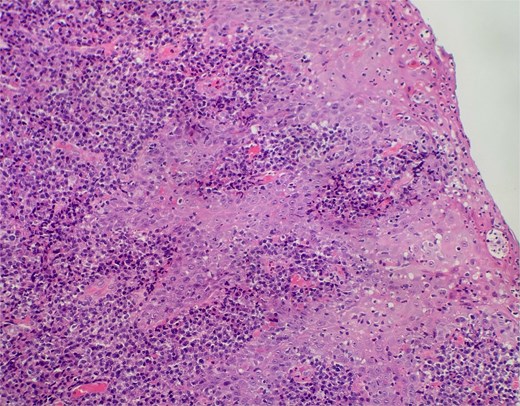

On clinical examination, harsh stridor with increased work of breathing was noted. Flexible nasoendoscopy demonstrated generalized supraglottic oedema with impending upper airway obstruction. Intravenous dexamethasone was commenced. A surgical tracheostomy with laryngeal biopsies under general anaesthetic was carried out. Histological examination (Figs 1 and 2) demonstrated hyperplastic, hyperkeratotic squamous mucosa with reactive atypia and an underlying dense polyclonal plasmocytic inflammatory infiltrate. No granulomata, prominent eosinophils, or stigmata of vasculitis were seen. Connective tissue disease screening demonstrated normal antinuclear antibody levels with positive perinuclear anti-neutrophil cytoplasmic antibodies. Anti-proteinase 3 levels returned as 3.7 IU/ml (range 0–1.9), while antimyeloperoxidase levels were normal. Rheumatology was consulted, and a provisional diagnosis of PCM was made. Serial laryngoscopy demonstrated resolution of the oedema, with the supraglottis regaining a normal appearance despite gradual tapering of the intravenous dexamethasone. A tracheostomy capping trial was successful. The patient was decannulated uneventfully and discharged on oral prednisolone. Three months later, he was maintained on 5 mg prednisolone—attempts to taper any further caused symptoms recurrence. Outpatient referral was made to Rheumatology for medical management with steroid-sparing therapy. Unfortunately, the patient was lost to follow-up due to failure to attend for outpatient review.

Slide from epiglottis specimen at index presentation showing squamous mucosa and underlying polyclonal plasmocytic infiltrate.